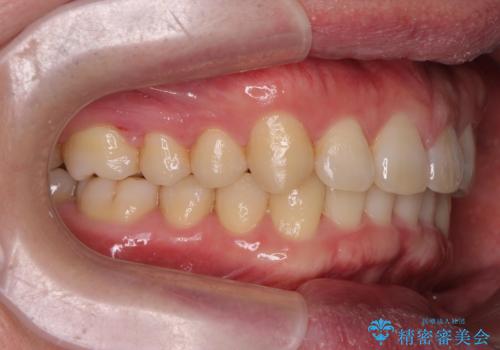

下の歯のがたつきが気になる。 インビザラン&ワイヤー部分矯正併用

- 下の歯が気になるとの事で来院。

左上の奥歯がシザーバイトがありワイヤーで部分的な矯正を行い、シザーバイトを改善した後にインビザラインで全体的な矯正治療を行いました。

歯のがたつきが改善され大変満足されました。